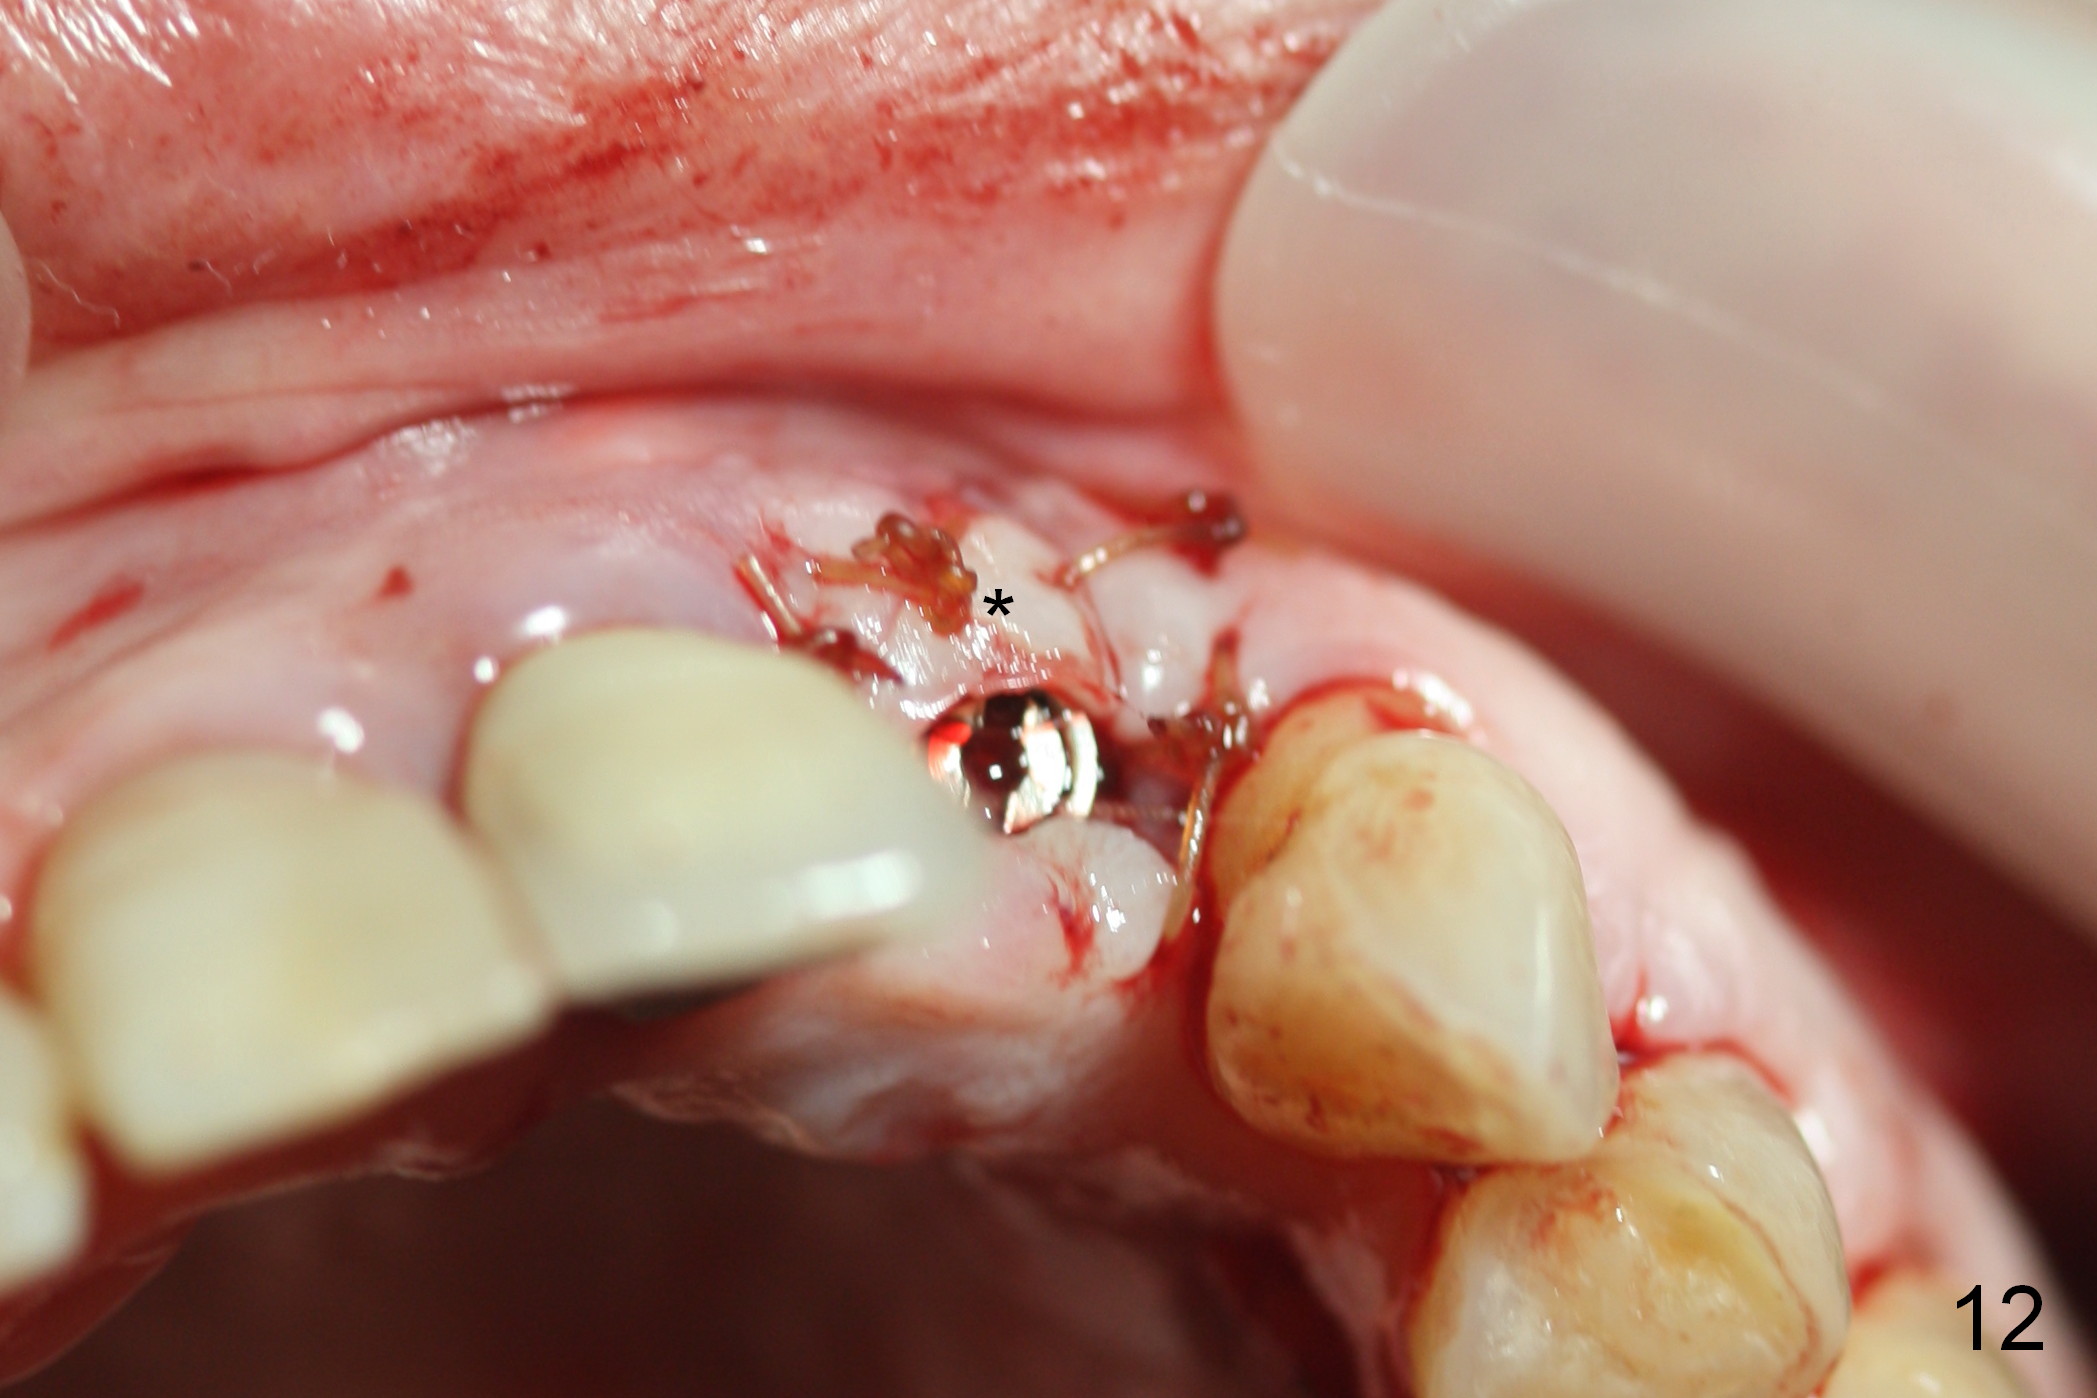

As expected, there is midbuccal tissue deficiency (Fig.9,10: 2 months postop). After discussion, a free gingival graft from the palate is placed (Fig.11,12 *). Two weeks later, the graft sloughs (Fig.13). A pedicled flap is designed (Fig.14) and transferred to repair the defect (Fig.15,16).